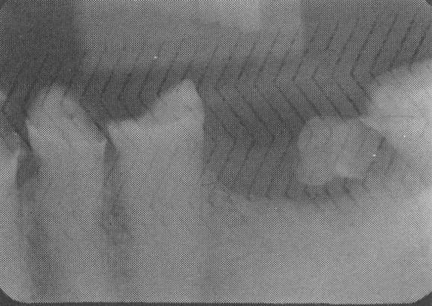

Herringbone pattern